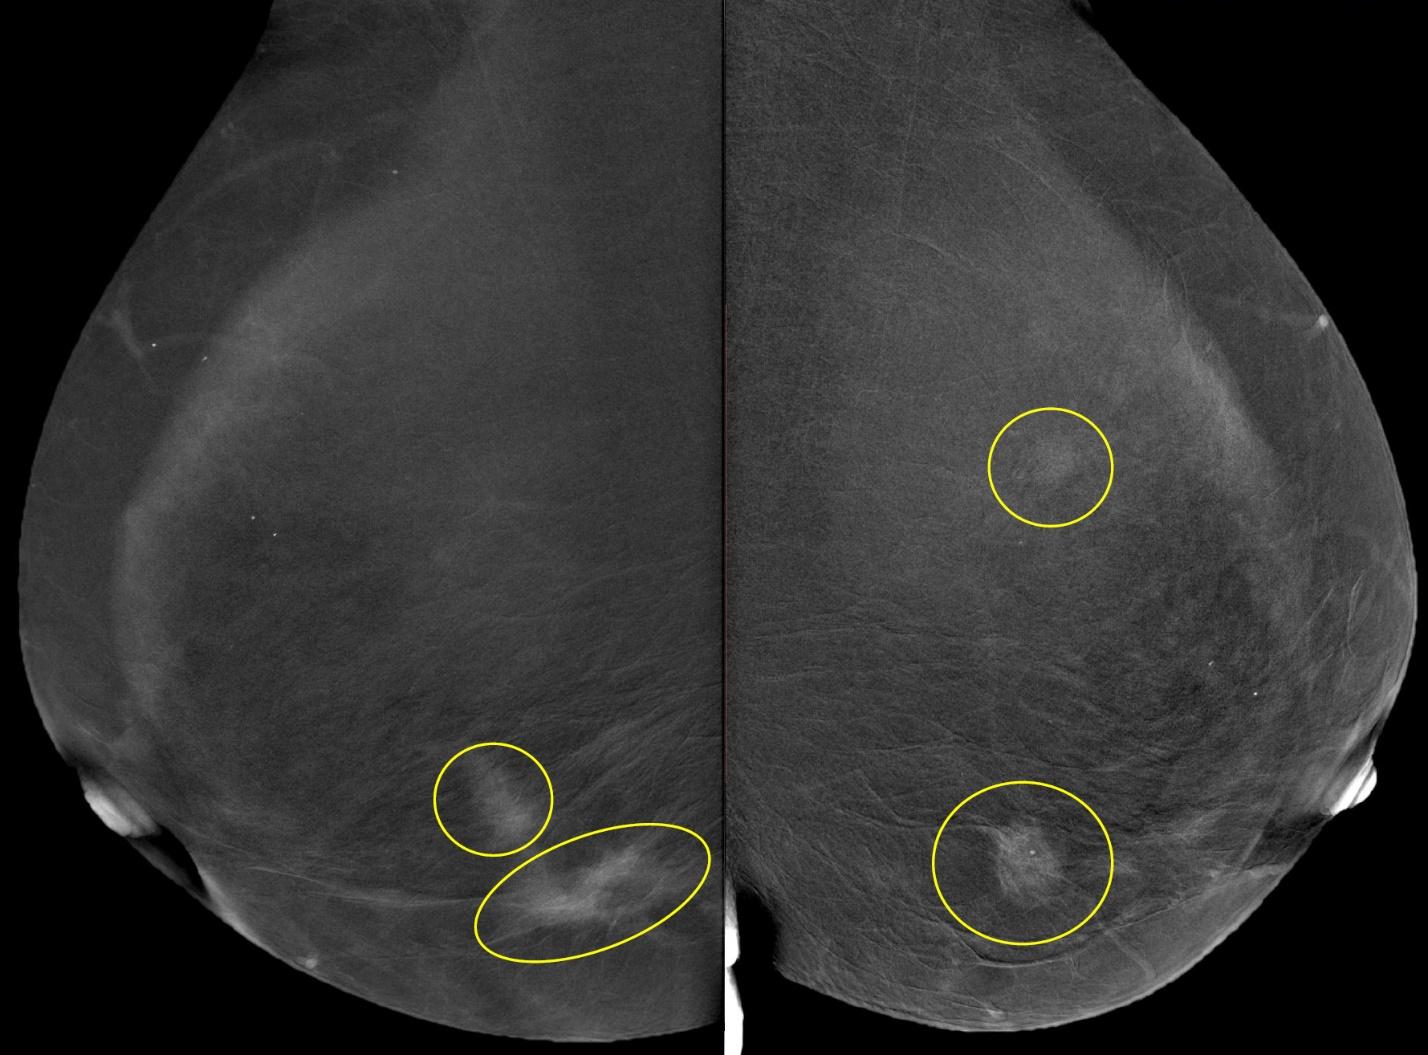

Шаг 8. Нужна ли функция цифрового томосинтеза (DBT)?